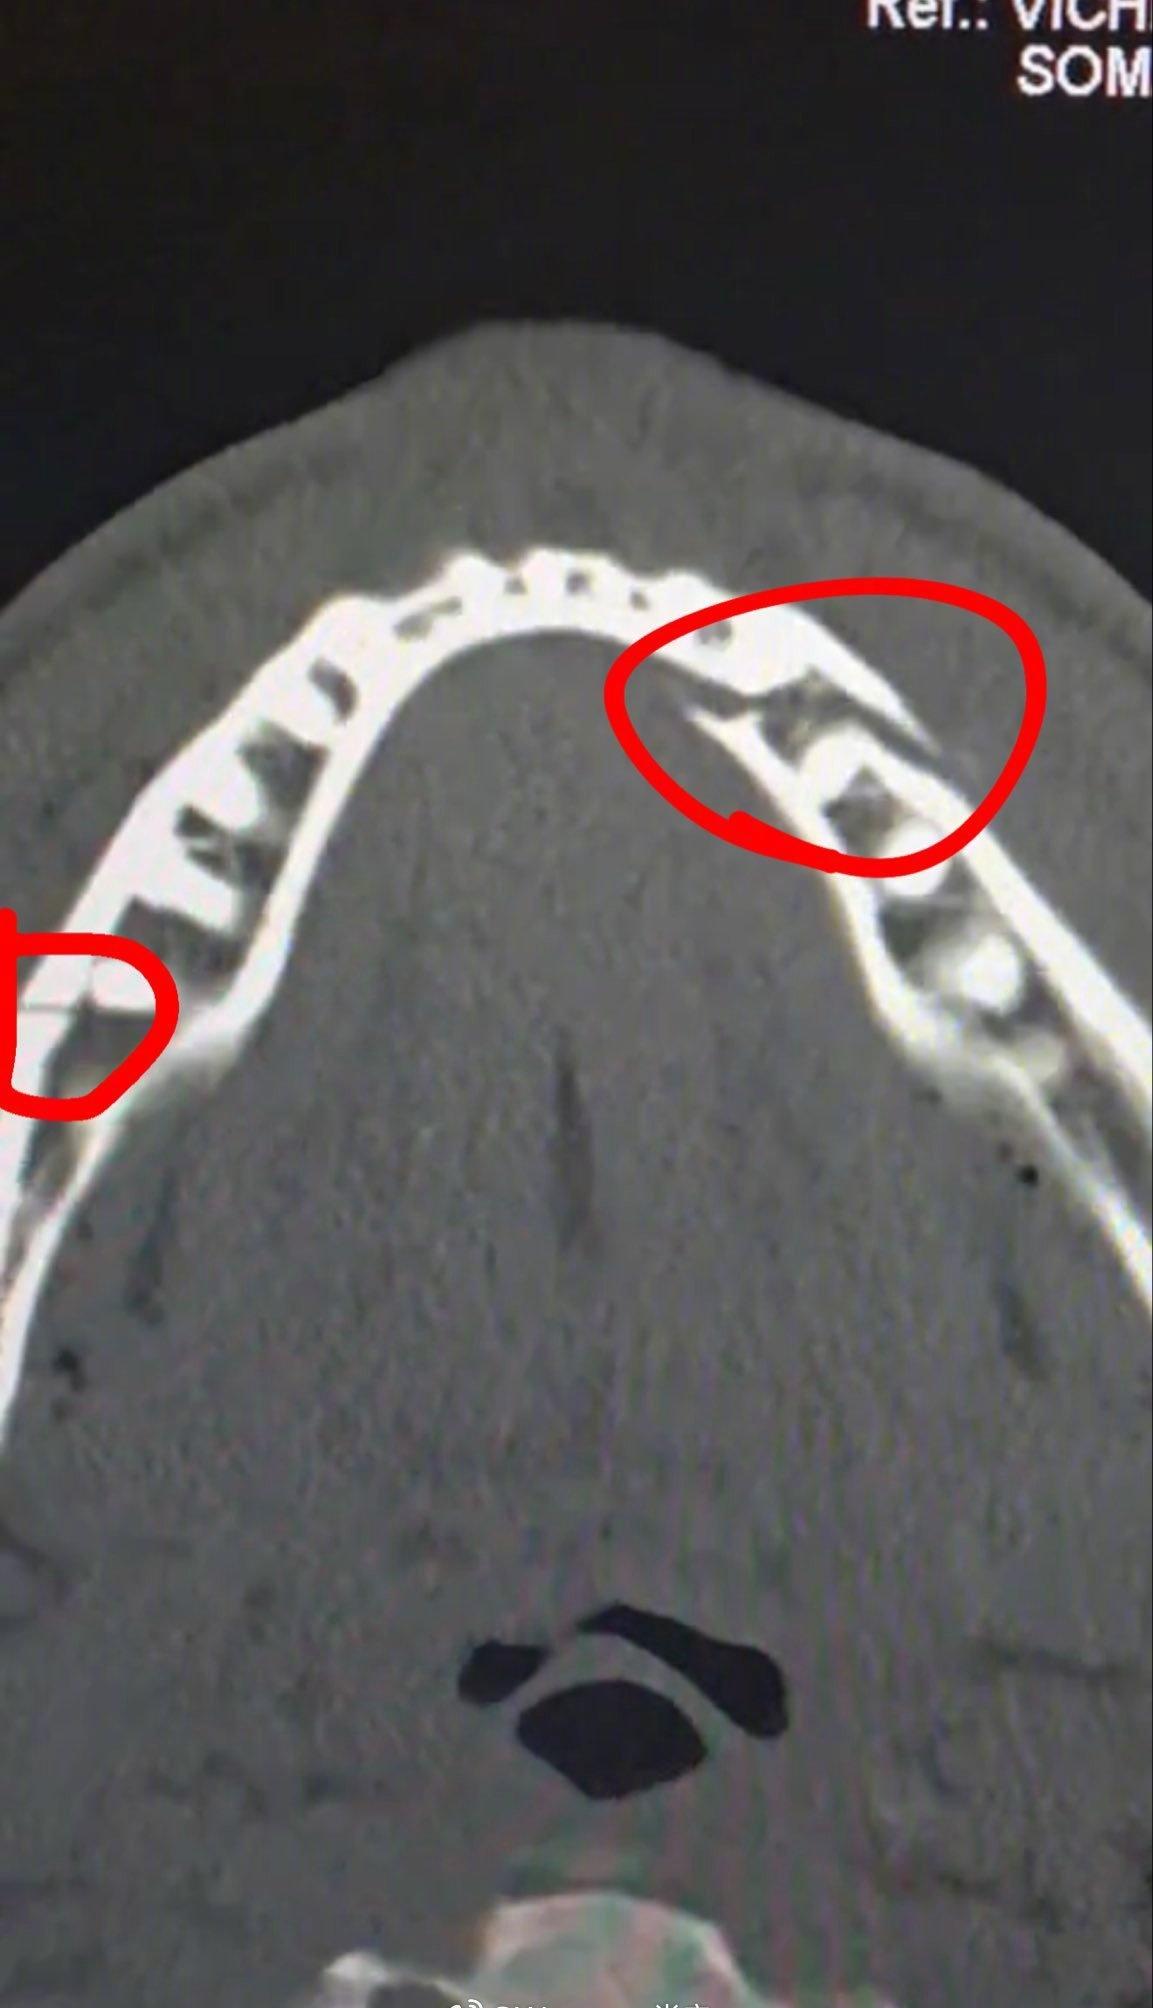

著名网红拳击手杰克·保罗以和各退役知名拳手比赛尤其击败58岁的泰森而出名,更是著名的MAGA、反女权主义和加密货币操作者。今晚他在和迈阿密前重量级拳王安东尼·约书亚对决时被一记右重拳打爆下颚骨,牙齿脱落,当时他面露恐惧的表情今晚火爆网络。杰克·保罗在被安东尼·约书亚击倒后,成功接受了下颌手术,包括在他的脸部两侧各植入两块钛板,并拔除了多颗牙齿。保罗接下来7天将只吃流质食物。